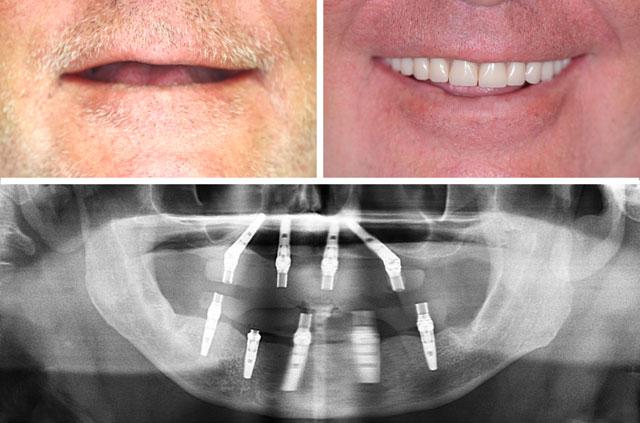

All-on-4 and immediate implant solutions for complete smile restoration. These cases showcase our expertise in full-arch rehabilitation with same-day teeth, providing patients with immediate functional and aesthetic results.

Each case demonstrates the transformative power of dental implants, from single tooth replacement to full-arch restoration. Our All-on-4 Teeth-In-A-Day technique provides immediate results and long-term stability.

All-on-4 is a revolutionary dental implant technique that uses just four strategically placed implants to support a full arch of replacement teeth. The posterior implants are angled at 30-45 degrees to maximize bone contact and avoid anatomical structures like the maxillary sinus or inferior alveolar nerve. This innovative approach allows for immediate loading with a temporary prosthesis, providing same-day teeth and eliminating the need for lengthy healing periods between procedures.